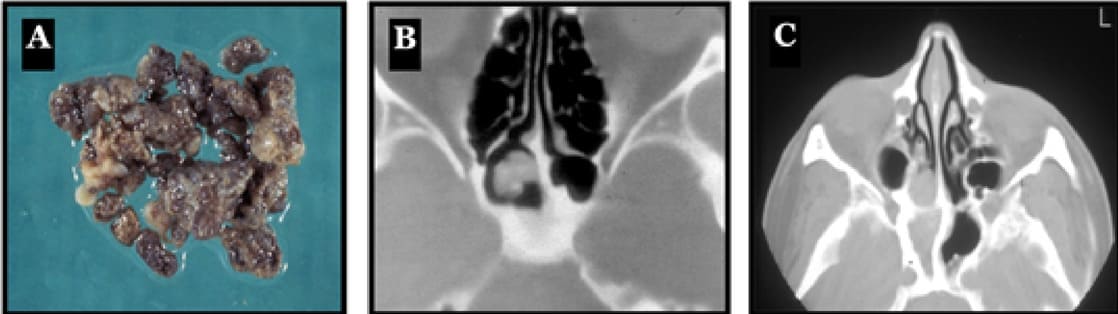

Figure 9:(A) Macroscopic view of a mycetoma shows grey and compact material. (B) Axial CT-scan of a mycetoma characterized by an opacity in the sphenoid sinus with surprisingly, a patent ostium. (C) Typical axial CT-scan of a fungal ball in the sphenoid sinus. The image reveals a polyp extruding from the ostium of the sphenoid cavity, a sclerosis of the bony walls and a complete opacity of the sphenoid sinus. In this case, no microcalcifications can be seen.